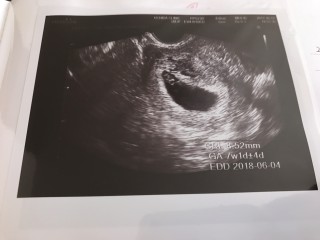

BTで授かっています。前週に胎芽、卵黄嚢、心拍確認。どれだけ大きくなってるかという今回はCRL8.52mmと小さい感じでしたが、特に何も言われないし、心拍もあるし、位置や向きのせいだろうと思うことに。そして翌週には19mmと問題なし。出血もわずかに時々みられていましたが、問題なし。普通に長時間勤務、夜勤もしていました。つわりで辛いので休みの日は何もしていませんでしたが。

一週間前6w5dで胎嚢の中身が空っぽでした。 半分諦めて受診した7w5dで心拍、卵黄のう、胎芽の全てが確認出来ました! のちの数週訂正でこの時8w3dとなります。 胎嚢の大きさ的には6w6dとなっています。